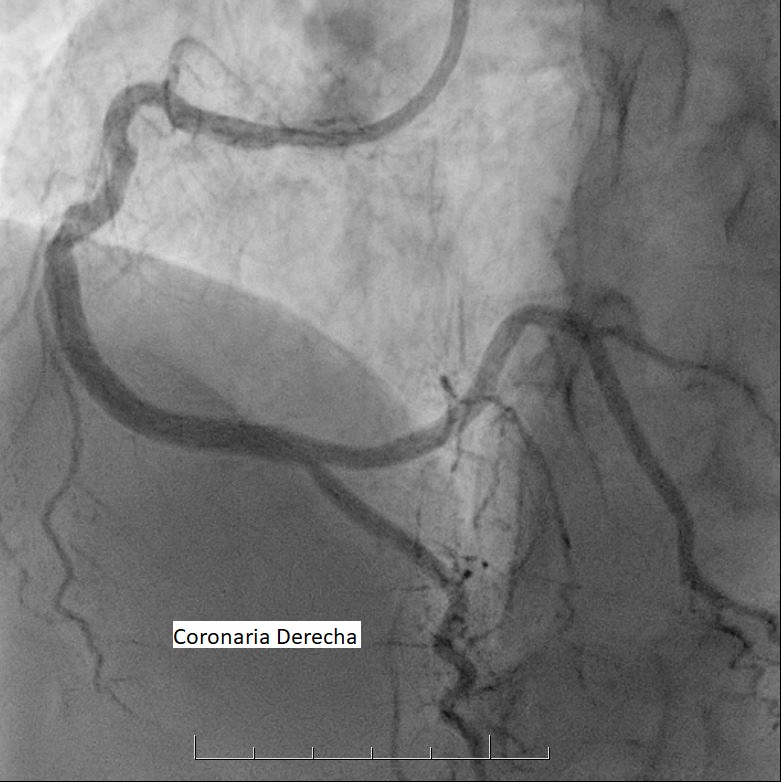

La sala donde te realizarán el estudio se encuentra a baja temperatura. Este procedimiento se efectúa con anestesia local y comienza con la introducción de un catéter por punción en una de las arterias de la muñeca o la ingle, de acuerdo a las características de cada persona.

Este catéter llega hasta las arterias coronarias y una vez allí se inyecta una sustancia de contraste, que permite visualizarlas y verificar si hay obstrucciones.